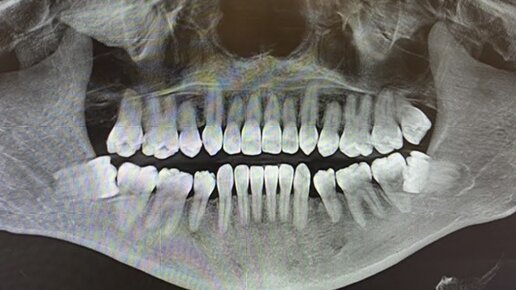

Не у всех и не всегда во рту развивается сценарий, когда 8-ки не хотят мирно жить. Но иногда наши врачи вынуждены удалять соседние 7-ки, потому что зубы мудрости растут не так как положено приличным зубам, а так, как могут. То есть не вверх, а полулежа в сторону соседа. Это не что иное, как медленный, тяжеловесный таран. В итоге страдает корень седьмого зуба. Как именно страдает? Он просто рассасывается под напором настырного зуба мудрости. А без корня не может устоять даже самая здоровая единица...